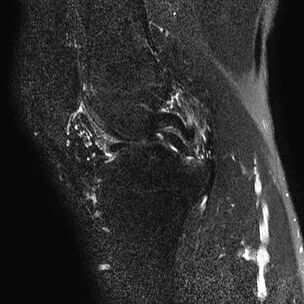

半月板水平撕裂

1、水平撕裂

2、较少见3、III级高信号与胫骨平台平行,到达半月板的游离缘或一侧关节面

(半月板水平撕裂)